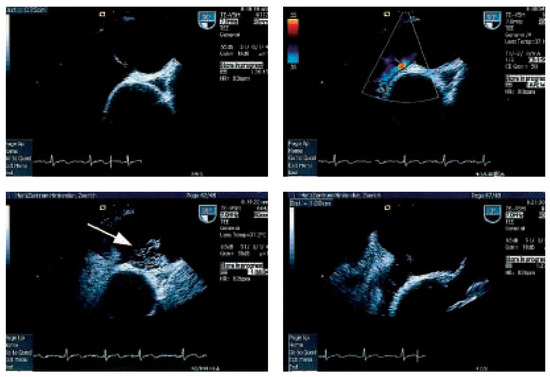

Platypnoe—Orthodeoxie: Eine Seltene Ursache Einer Lageabhängigen Dyspnoe und Arteriellen Hypoxämie

by Urs N. Dürst, Manfred Ritter, Beat Walder and Franz R. Eberli

Cardiovasc. Med. 2005, 8(10), 370; https://doi.org/10.4414/cvm.2005.01130 - 28 Oct 2005

Platypnea—orthodeoxia: a rare cause of positional dyspnea and arterial hypoxaemia. We report a case of an 83-year-old female patient, that developed positional dyspnea after a fall complicated by a thoracic spine compression fracture. In upright position the dyspnea was disabling occurring already with [...] Read more.

Platypnea—orthodeoxia: a rare cause of positional dyspnea and arterial hypoxaemia. We report a case of an 83-year-old female patient, that developed positional dyspnea after a fall complicated by a thoracic spine compression fracture. In upright position the dyspnea was disabling occurring already with normal daily activities, such as dressing. The dyspnea could be relieved by recumbancy. In supine position the patient’s arterial saturation was 94% and decreased to 86% in upright position. Transoesophageal echocardiography revealed an atrial septal defect with bi-directional shunt. The atrial septal defect was closed percutaneously with an Amplatzer-Septal-Occluder® 20 mm. Following the occlusion of the atrial septal defect, arterial oxygen saturation remained stable and the positional dyspnea disappeared. Full article